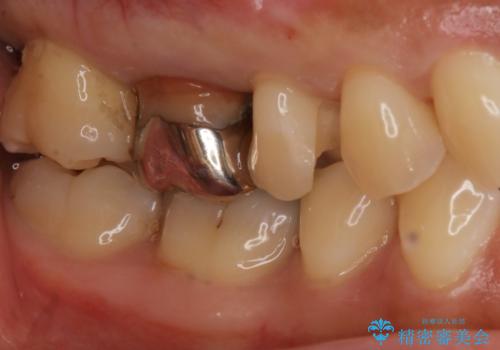

- 右上4、5の歯がしみるのを治したいという主訴で来院されました。精査の結果隣接面う蝕と診断し、適合がよく見ためも良いセラミックインレーでの治療を行いました。

セラミックインレーを入れた後は歯がしみることはなくなり、白く丈夫な被せ物が入り満足いただけました。